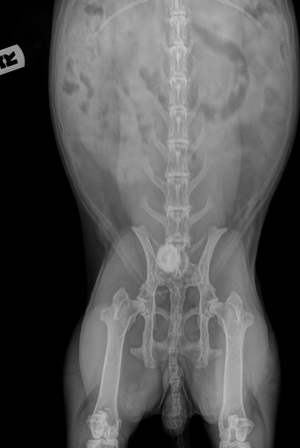

Röntgen: Auf Röntgenbildern sind Kalziumablagerungen als schneeweiße "Wolken" und Steine als solide weiße "Kreise" deutlich erkennbar. Auch Kalziumablagerungen in der Aorta und im Knochengewebe sind deutlich erkennbar. Im Gegensatz zum Ultraschall sind hier außerdem auch Steine sichtbar, die bereits in die Harnröhre gewandert sind. Um die Lokalisation zu bestimmen, sind zwei Aufnahmen aus unterschiedlichen Ebenen notwendig.

Da im Falle einer Blasenkalzinose häufig auch der übrige Harntrakt betroffen ist, sollte unbedingt ein Ganzkörperröntgen angefertigt und beim Ultraschall auch die Nieren mit kontrolliert werden.